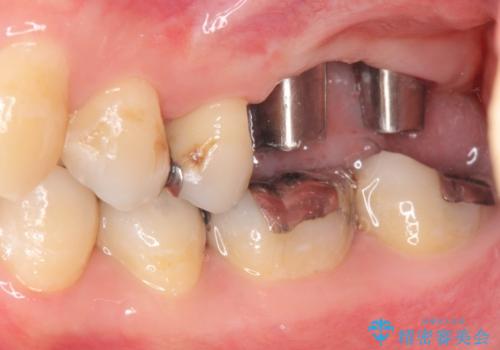

上顎奥歯のインプラント治療

- 奥歯を失い咬合機能の回復のためインプラント治療を希望され来院されました。

奥歯を2本失うと、他の歯の負担が増加し残っている歯の状態が悪くなるリスクがあります。

しっかりと咬合機能の回復できるインプラント治療を計画します。

- 88万円(インプラント×2・チタンカスタムアバットメント×2・ジルコニアクラウン×2・仮歯×2)費用は治療当時の料金となります

しっかりと食事ができるようになり、当院のインプラント治療に満足いただくことができました。